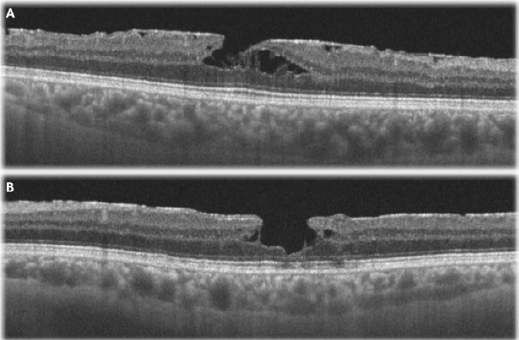

A 61-year-old patient without any significant past medical history first presented to our service two years ago for an eye consult. At that time, the visual acuity was unaffected, and the patient was diagnosed with BE epiretinal membrane, showing no tomographic signs of retinal layers’ disruption. Two years later, the patient started to complain of LE metamorphopsia and VA drop. On the current examination, Snellen’s VA was 6/6 in the RE and 6/19 in the LE. The intraocular pressures and the anterior segments were normal in both eyes. Fundoscopy revealed a glisteny membrane on the surface of the retina and a round-elliptical hole with medium depth and no deposits located directly in the center of the macula in both eyes. Spectral-domain optical coherence tomography (OCT) showed morphological changes of the foveal contour with epiretinal membranes, disruption of the inner retinal layers, intraretinal splitting and intraretinal cysts, more advanced in the LE compared to the RE (Figure 1). Due to the patient’s symptoms, visual acuity drop and the disorder’s anatomical progression, the patient’s LE was surgically treated using the internal limiting membrane inverted flap technique, as described before. There was rapid improvement of the anatomical and functional features of the macula (Figure 2), the LE VA reaching 6/9.5 at one-month visit.

Figure 1: Preoperative macular optical coherence tomography with horizontal scans of the fovea of the

A. Right eye and

B. Left eye.